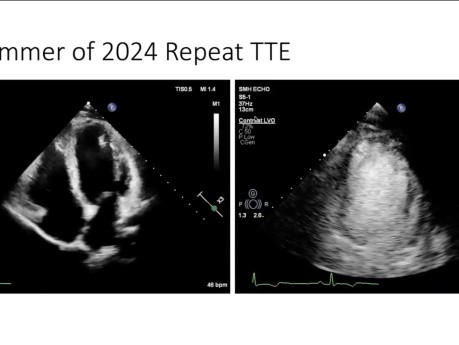

Ponad prawą komorą: nawracające zapalenie mięśnia...

Prelegent: Lek. Ryan Sless, PGY 5, Univeristy of Toronto. Cele: 1. Przedstawienie przypadku nawracającego zapalenia mięśnia sercowego i omówienie momentu, kiedy należy rozważyć inne etiologie. 2. Przegląd...